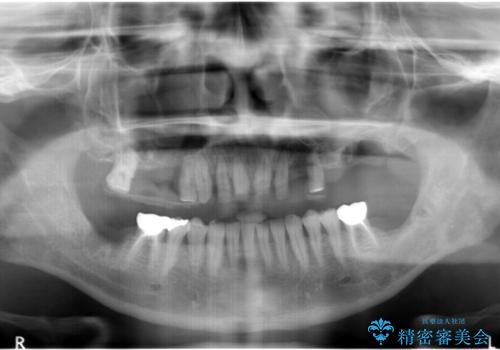

- 他院で上顎は全て抜歯し、入れ歯にする必要があると言われ相談に来院されました。

検査の結果、重度の歯周病であることから保存が難しい歯は抜歯を行いインプラントを、残すことが可能な歯には再生治療を含めた歯周病治療を行いより多くの歯を残す歯周病治療を計画します。